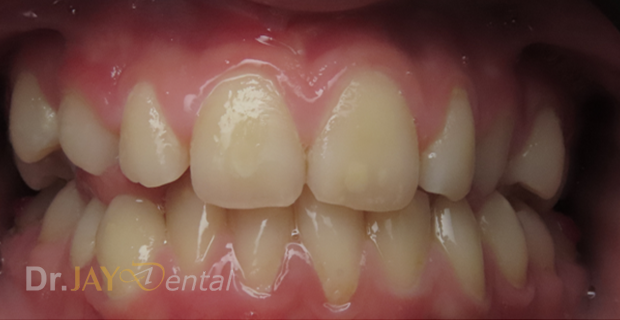

Patient had issue with spacing needed for erupting teeth , patient still going through treatment. After picture : in 6 months with Myofunctional therapy and tongue tie revision , jaws are widening and teeth are having space to erupt

Before

After